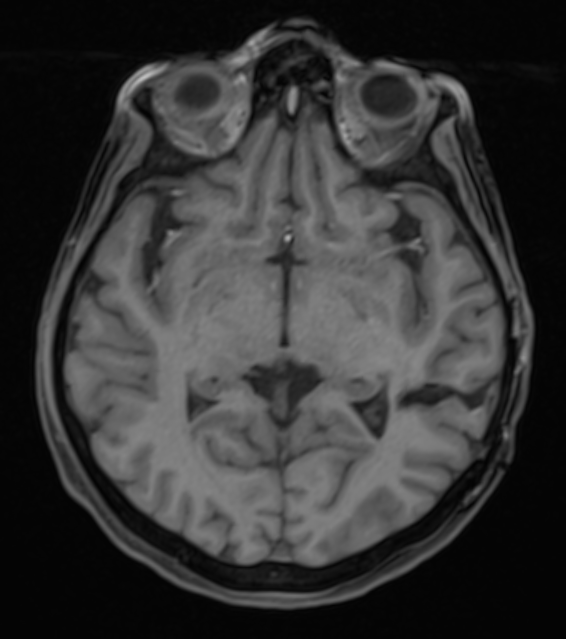

cavernome temporal

Figure 2. Absence de reliquat du cavernome, à 6 mois post-opératoire